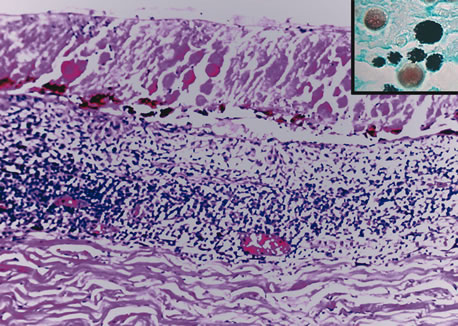

Retinochoroiditis

Necrotizing retinitis with secondary choroiditis is seen in protozoal infections such as toxoplasmosis or in herpetic infections. Infection with Toxoplasma gondii leads to retinitis and secondary choroiditis (Fig. 25), usually granulomatous.127 Congenital infection can be acquired in utero by transplacental transmission of the parasite from the infected mother to the fetus.128 Acquired disease occurs after ingestion of oocysts or tissue cysts.129–132 The congenital form of infection leads to atypical macular colobomas. Reactivation of the infection is caused by release of organisms that have remained dormant in the margins of old congenital retinal scars.133 The slowly proliferating form of the organism, termed the bradyzoite, can be seen in cysts. The rapidly multiplying form, termed the tachyzoite, may be difficult to identify in an infected retina or in immunocompetent individuals, but they are frequently seen in the retinitis of immunocompromised hosts.134 Active infection usually causes focal retinal opacification and an intense vitritis. These findings may give the appearance of a “headlight in a fog” in an immunocompetent person. In contrast, this clinical presentation is rare in patients with AIDS, in whom diffuse retinitis is observed with non-granulomatous choroiditis.134

Fig. 25. Toxoplasma retinochoroiditis. Necrotic retina shows cysts of toxoplasma gondii, and the choroid reveals granulomatous inflammation. (Hemotoxylin-eosin ×65.) Inset (Gomori methenamine silver ×160) shows cysts of the organisms.